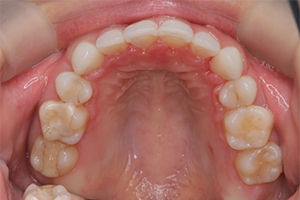

矯正治療のCASE 05

Before

After

-

- 主訴

- 歯並びがガタガタしていて清掃しにくい

- 治療内容

- ラビアル矯正(表側)

抜歯あり

- 治療費用

- 88万円~(税込)

- 治療期間

- 20か月

【リスク・副作用】

歯の痛み、口内炎、歯磨きがしにくいことによるむし歯や歯周病のリスク、歯根吸収や歯の変色、後戻りなどの副作用があります。